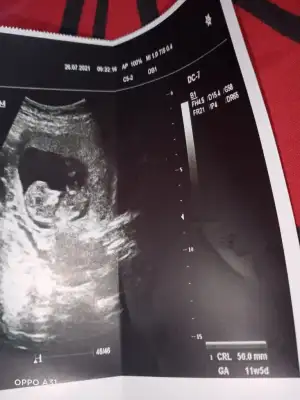

Kız gibi sanki emin olamadımEki Görüntüle 2892053 Eki Görüntüle 2892054 @Ikra meyra acaba müsait olunca bakar mısın? 11+6 oldu belli olur mu biraz?

Teşekkür ederimKız gibi sanki emin olamadım